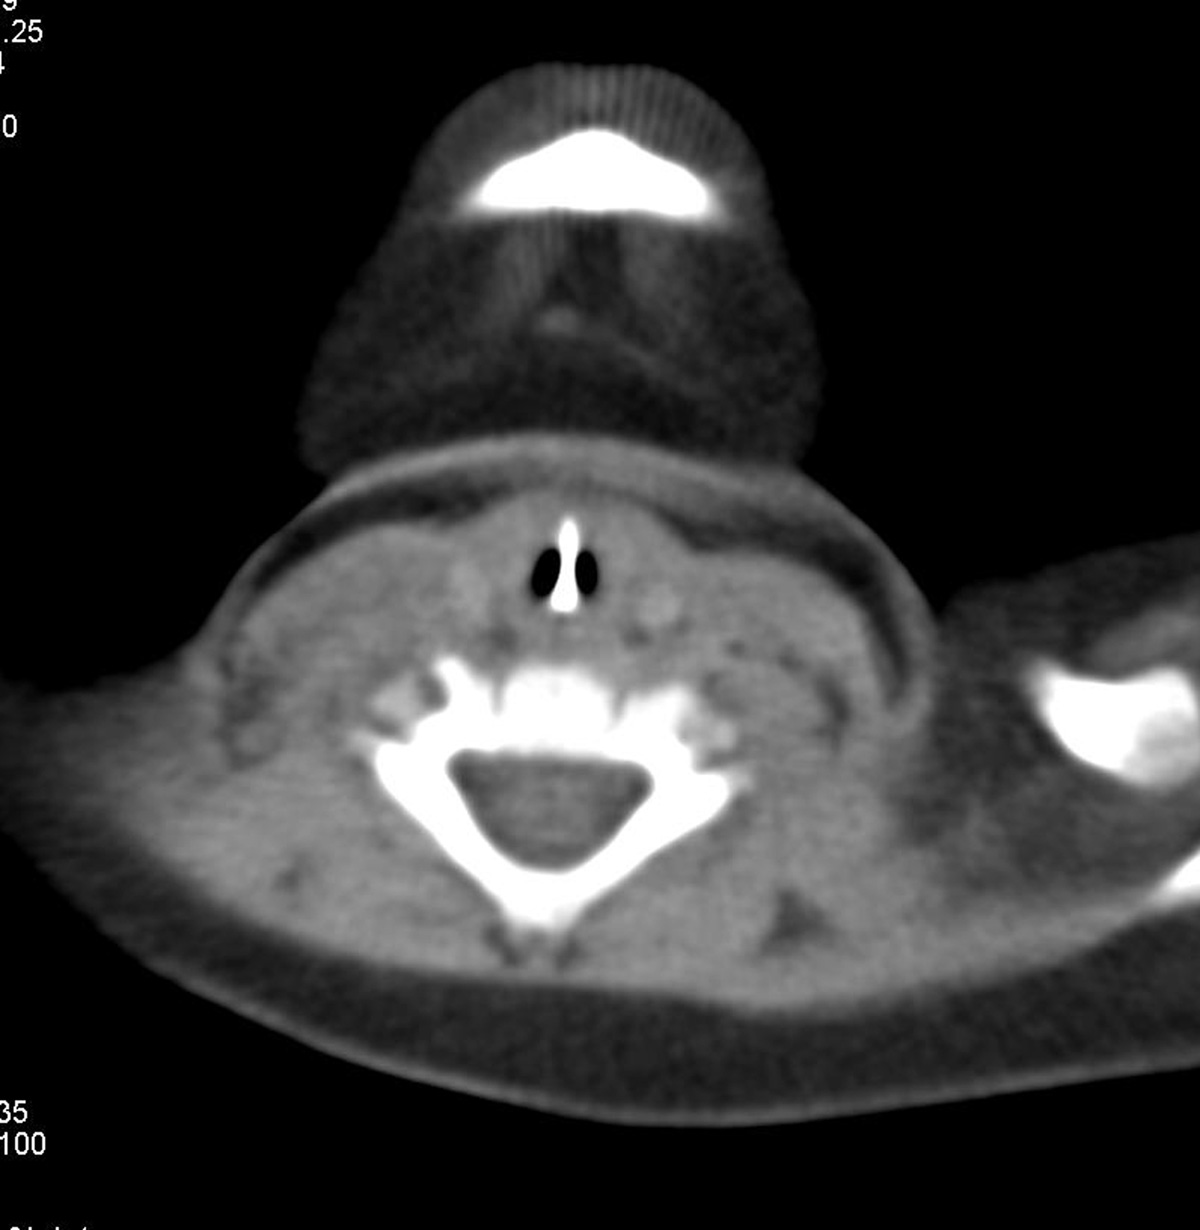

CT scan axial soft tissue window of 7 Months old male child with history of foreign body aspiration with asymptomatic baby showing linier metallic foreign body oriented vertically in the center with patent lumen on either side.